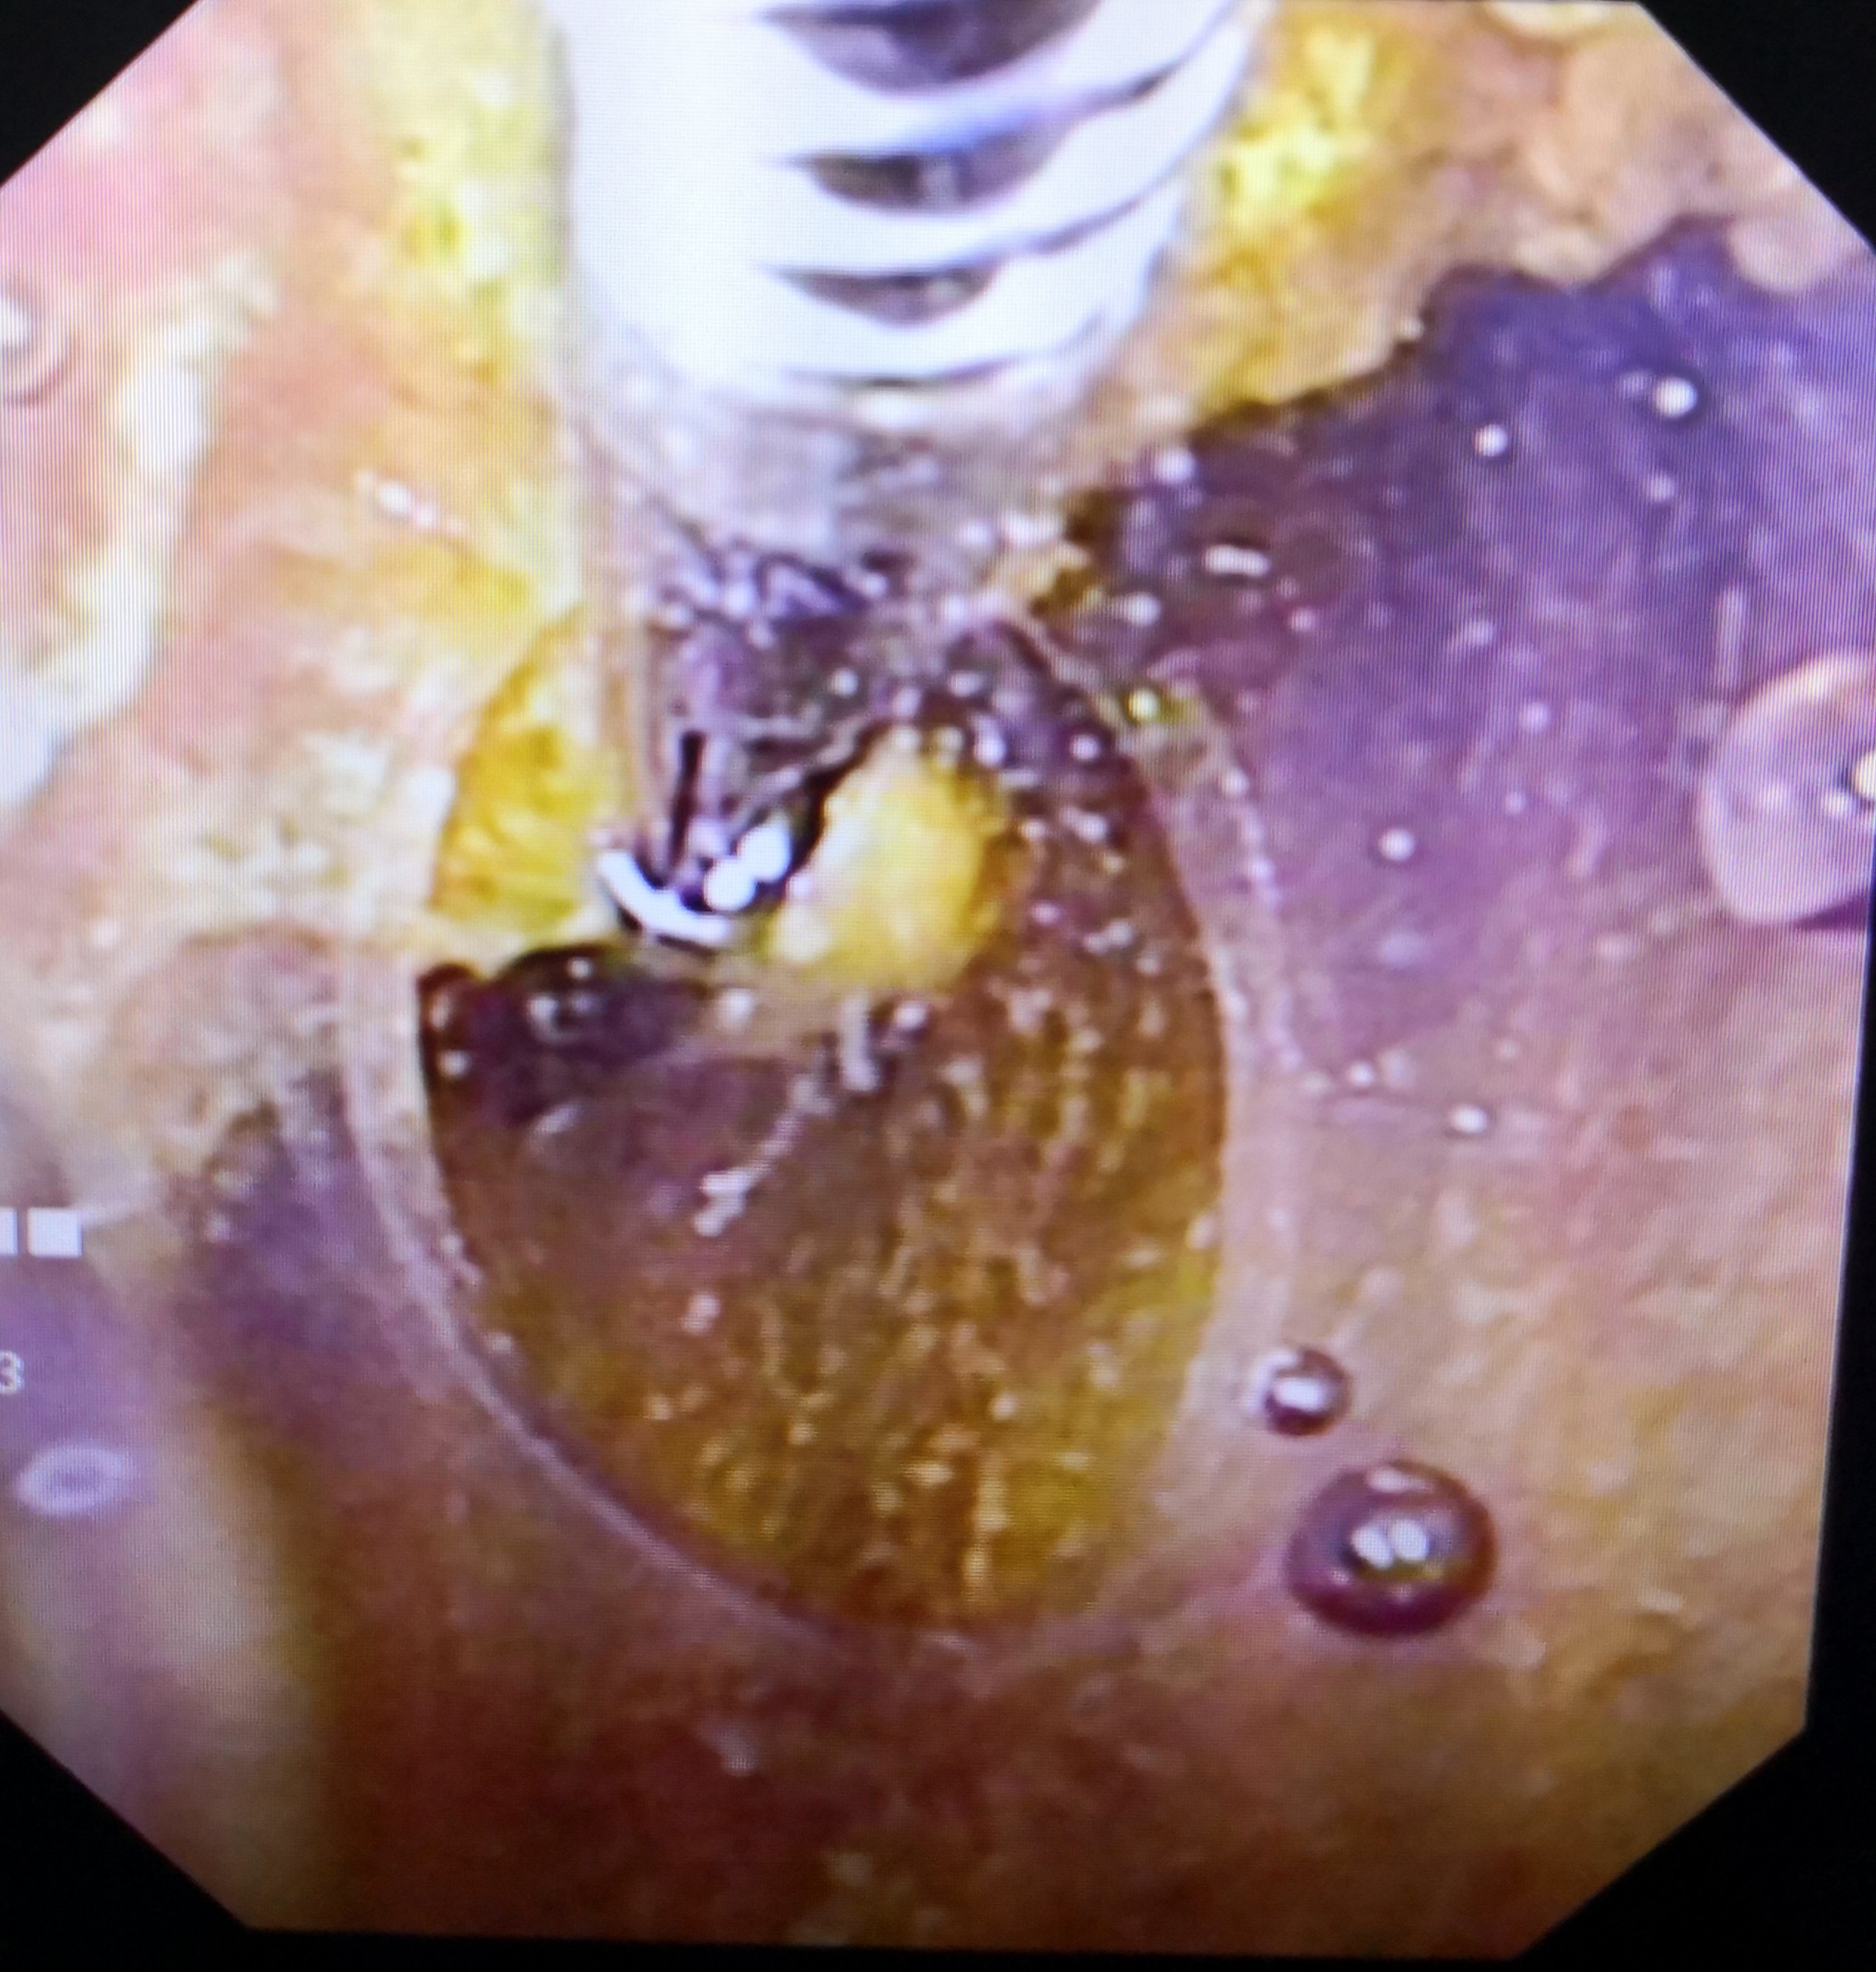

尤其是多发的胆囊息肉的病人,也是进行手术切除的指征,可以选择传统的开放手术,也可以选择腹腔镜下的手术治疗在处理胆囊三角的时候要辨认好解剖关系,手术以后常规的抗感染,对症治疗早期离床活动,预防肠粘连和肠梗阻的;不同类型的胆囊息肉病因也不相同多数患者无明显自觉症状,少数患者可能出现右上腹不适恶心呕吐食欲不振等表现无明显症状息肉体积较小的患者可暂不进行特殊处理定期复查即可,其余患者可通过手术进行治疗治疗 治。

临床中并没有胆囊息肉的最佳治疗方法,胆囊息肉的治疗方法包括日常护理药物治疗和手术治疗等,需要根据患者症状息肉大小以及位置等情况,由专业医生结合实际病情制定治疗方案1日常护理如果胆囊息肉较小且患者无其他不适;对于需要治疗的胆囊息肉,目前临床上主要分为药物治疗和手术治疗两种方法药物治疗主要适合于胆固醇性息肉的病人,因为胆固醇性息肉的形成原因,主要是胆汁中胆固醇含量相对增多或者说胆酸相对不足,引起了胆固醇过饱和,变成了结晶。

胆囊息肉的治疗分为饮食及生活方式指导药物治疗及手术治疗,根据症状息肉大小及形态位置等决定1饮食及生活方式指导规律饮食吃好早餐降低胆固醇摄入量,尤其是晚上,应避免进食高胆固醇类食品,如鸡蛋尤其是;早期如果能切除,化疗或放疗作用较小,则手术是首选治疗方法局部晚期肿瘤可累及十二指肠幽门肝曲胆道系统在这些情况下,肿瘤与受累器官一起切除,预后较差因此还是要加强胆囊癌早诊断早治疗的必要性胆囊息肉手术的。

1、对于胆囊息肉的治疗,目前主要以手术切除胆囊为主如果息肉直径大于1厘米,息肉持续增长,单发的息肉基底增厚以及并发有胆囊炎,胆囊结石等情况的可考虑手术治疗,其余的可暂时不做处理,定期复查彩超即可。

5、可以通过超声造影或者增强CT核磁进行诊断胆囊息肉的手术指征是息肉直径超过1cm,考虑腺瘤性息肉存在癌变风险的时候或者合并胆囊结石反复发作的胆绞痛也要考虑手术治疗,其它无症状的多发的胆固醇性息肉采取定期检查。